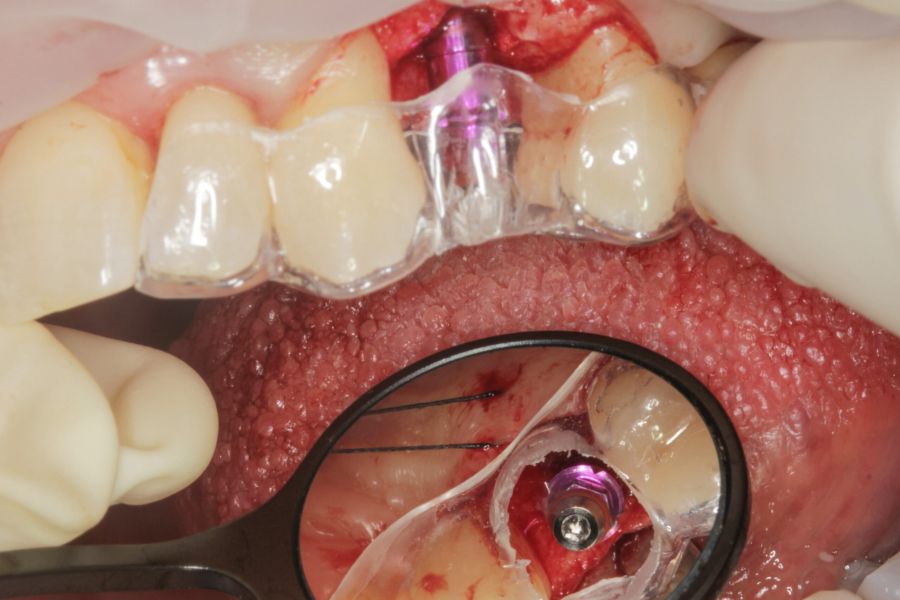

Todas las cirugías fueron realizadas por un único cirujano bajo anestesia local, tras un diagnóstico previo del lecho óseo mediante tomografía volumétrica (CBCT) procesada con un software específico de planificación implantológica (BTI-Scan III). La preparación del lecho implantario se llevó a cabo siguiendo la técnica de fresado biológico a bajas revoluciones descrita por Anitua y cols.19.

En cuanto a la rehabilitación protésica, en todos los casos se utilizó una prótesis atornillada con transepitelial para prótesis unitaria. La supervivencia de las prótesis fue del 100%, sin encontrarse fracaso en ninguna de ellas al igual que los implantes, con un tiempo de seguimiento de tres años. Durante el primer año, en las visitas de control, ninguno de los implantes mostró sangrado al sondaje ni inflamación de los tejidos periimplantarios. La media de la pérdida ósea en este punto fue de 0,32 mm (+/- 0,60) y la media de la pérdida ósea distal de 0,31 (+/- 0,48). A los dos años, no se registraron tampoco signos inflamatorios en ninguno de los implantes y la pérdida ósea mesial del conjunto fue de media de 0,38 mm (+- 0,54) y la distal de 0,64 mm (+/- 0,70). En la última visita a los 3 años, los tejidos periimplantarios siguieron estables, sin signos de inflamación y la media de la pérdida ósea mesial fue de 0,40 mm (+/- 0,53) y la distal de 0,69 (+/- 0,55) (Figura 5). En las Figuras 6-12 se muestra uno de los casos incluidos en el estudio.